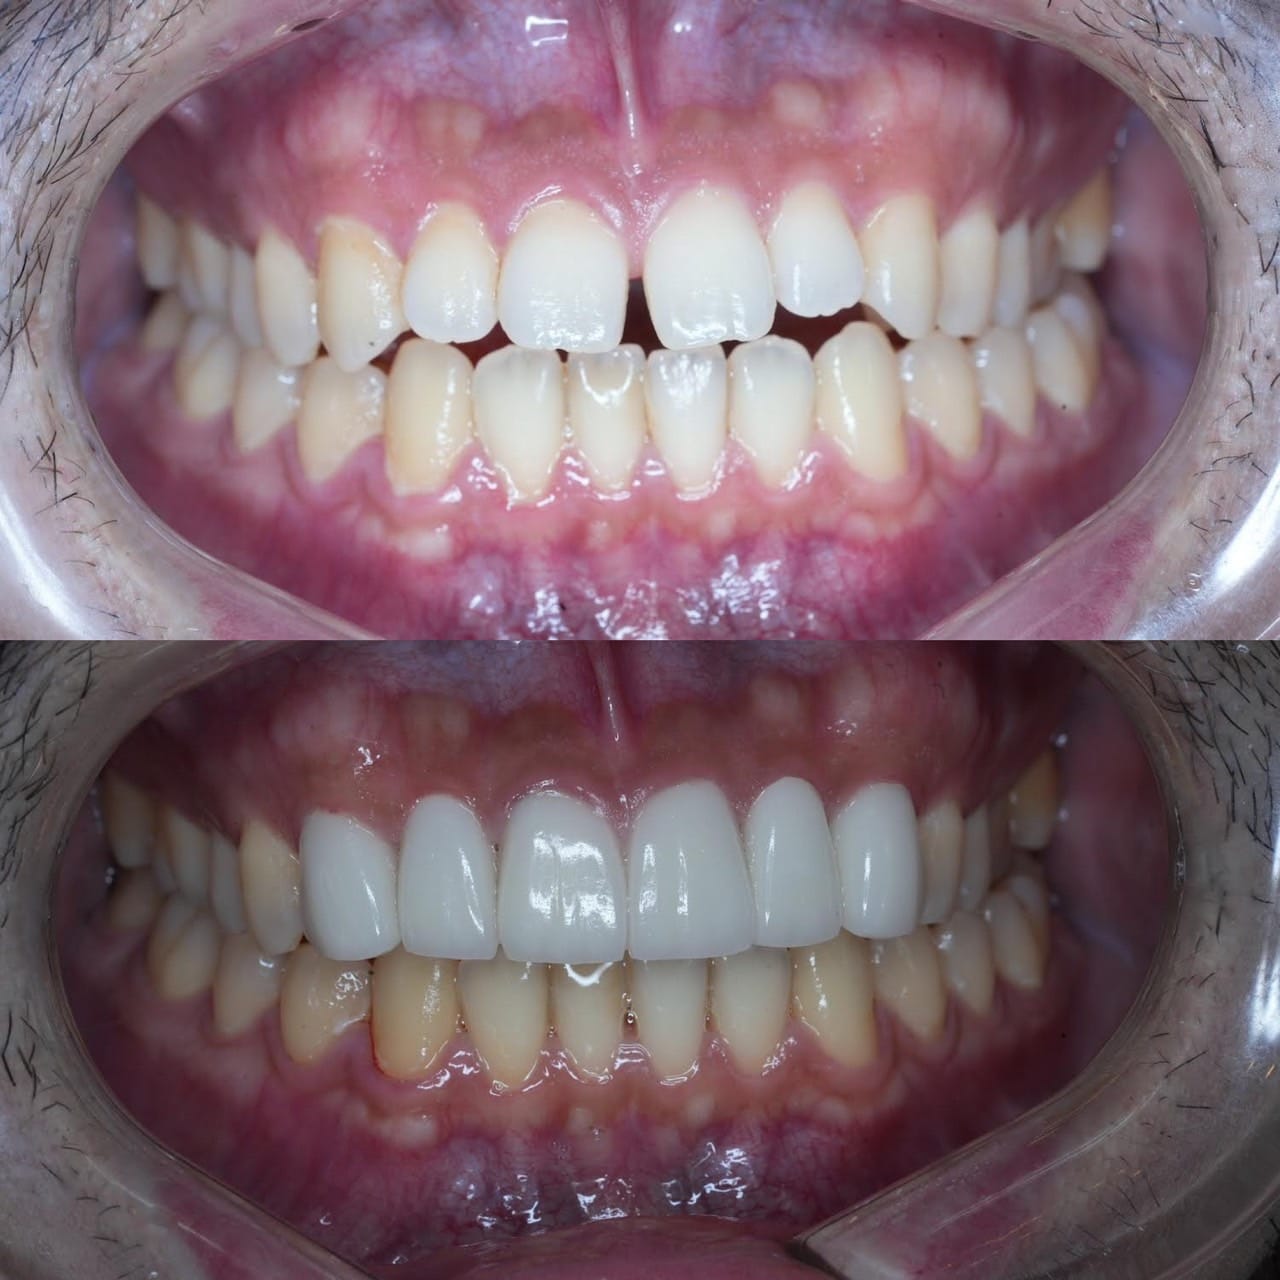

メジャーリーグでも活躍した元プロ野球選手の山口俊さんのセラミック治療を担当いたしました。

「他院で治療を受けたセラミックが欠けた」というのが主訴でしたが、よく診察するとセラミック欠けただけではなく、被せ物がしっかりと合っていないことが原因で歯茎の腫れがあり、歯石や汚れもつきやすい状態でした。また、歯列も若干歪んでいたので、この機会に全て治療いたしました。

治療後は透明感のある白さで、綺麗な歯並びになりました。また、セラミックをきちんと綺麗に削って適合よくセットしたことにより、歯茎の腫れも改善しました。

セラミックを入れた所の歯茎が腫れていて悩まれてる方はぜひご相談ください。

綺麗に削って適合よくセラミックをしてあげれば必ず改善します。